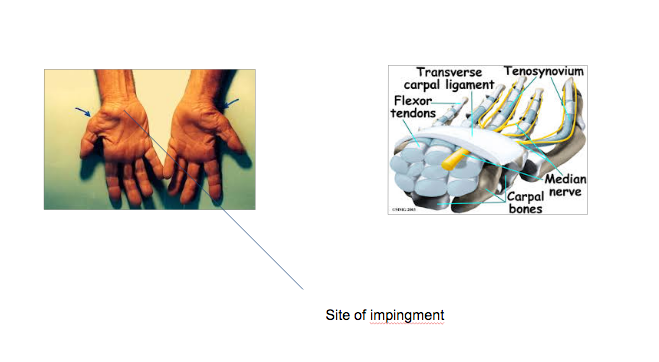

Where is the site of impingement for Carpal Tunnel/Median Nerve?

Most common peripheral nerve compression neuropathy

1.

- radial three digits

- +/- the ring finger-

2. they will say the whole hands numb besides the small finger.

3. Distal the the site of impingement - tap right here for stimualtion

4. Thenar muscle- won’t be able to palmarly adduct. Push against my thumb.

Carpal Tunnel/Median Nerve

- The blood supply gets cut off and that’s why they have symptoms?3

- What dz is associated with median nerve compression?

- What test?

- First line tx?

- 2nd line?

- 3rd line?

1.

- Inflammation/tendonitis

- Arthririts

- (less commonly fractures)

2. Diabetes- associated with peripheral nerve compression because of the glycosylation- gets thicker

3. Modified phalens- take fingers and push on carpal tunnel and then bend and squeeze

4. TX; - NSAIDS/aleve, with PPI

- Go get a splint (night time) > make sure hand is straight and not extended back.

5. 2nd line: cortisol

6. 3rd line: carpal tunnel release- indications: muscle wasting, persistent numbness.